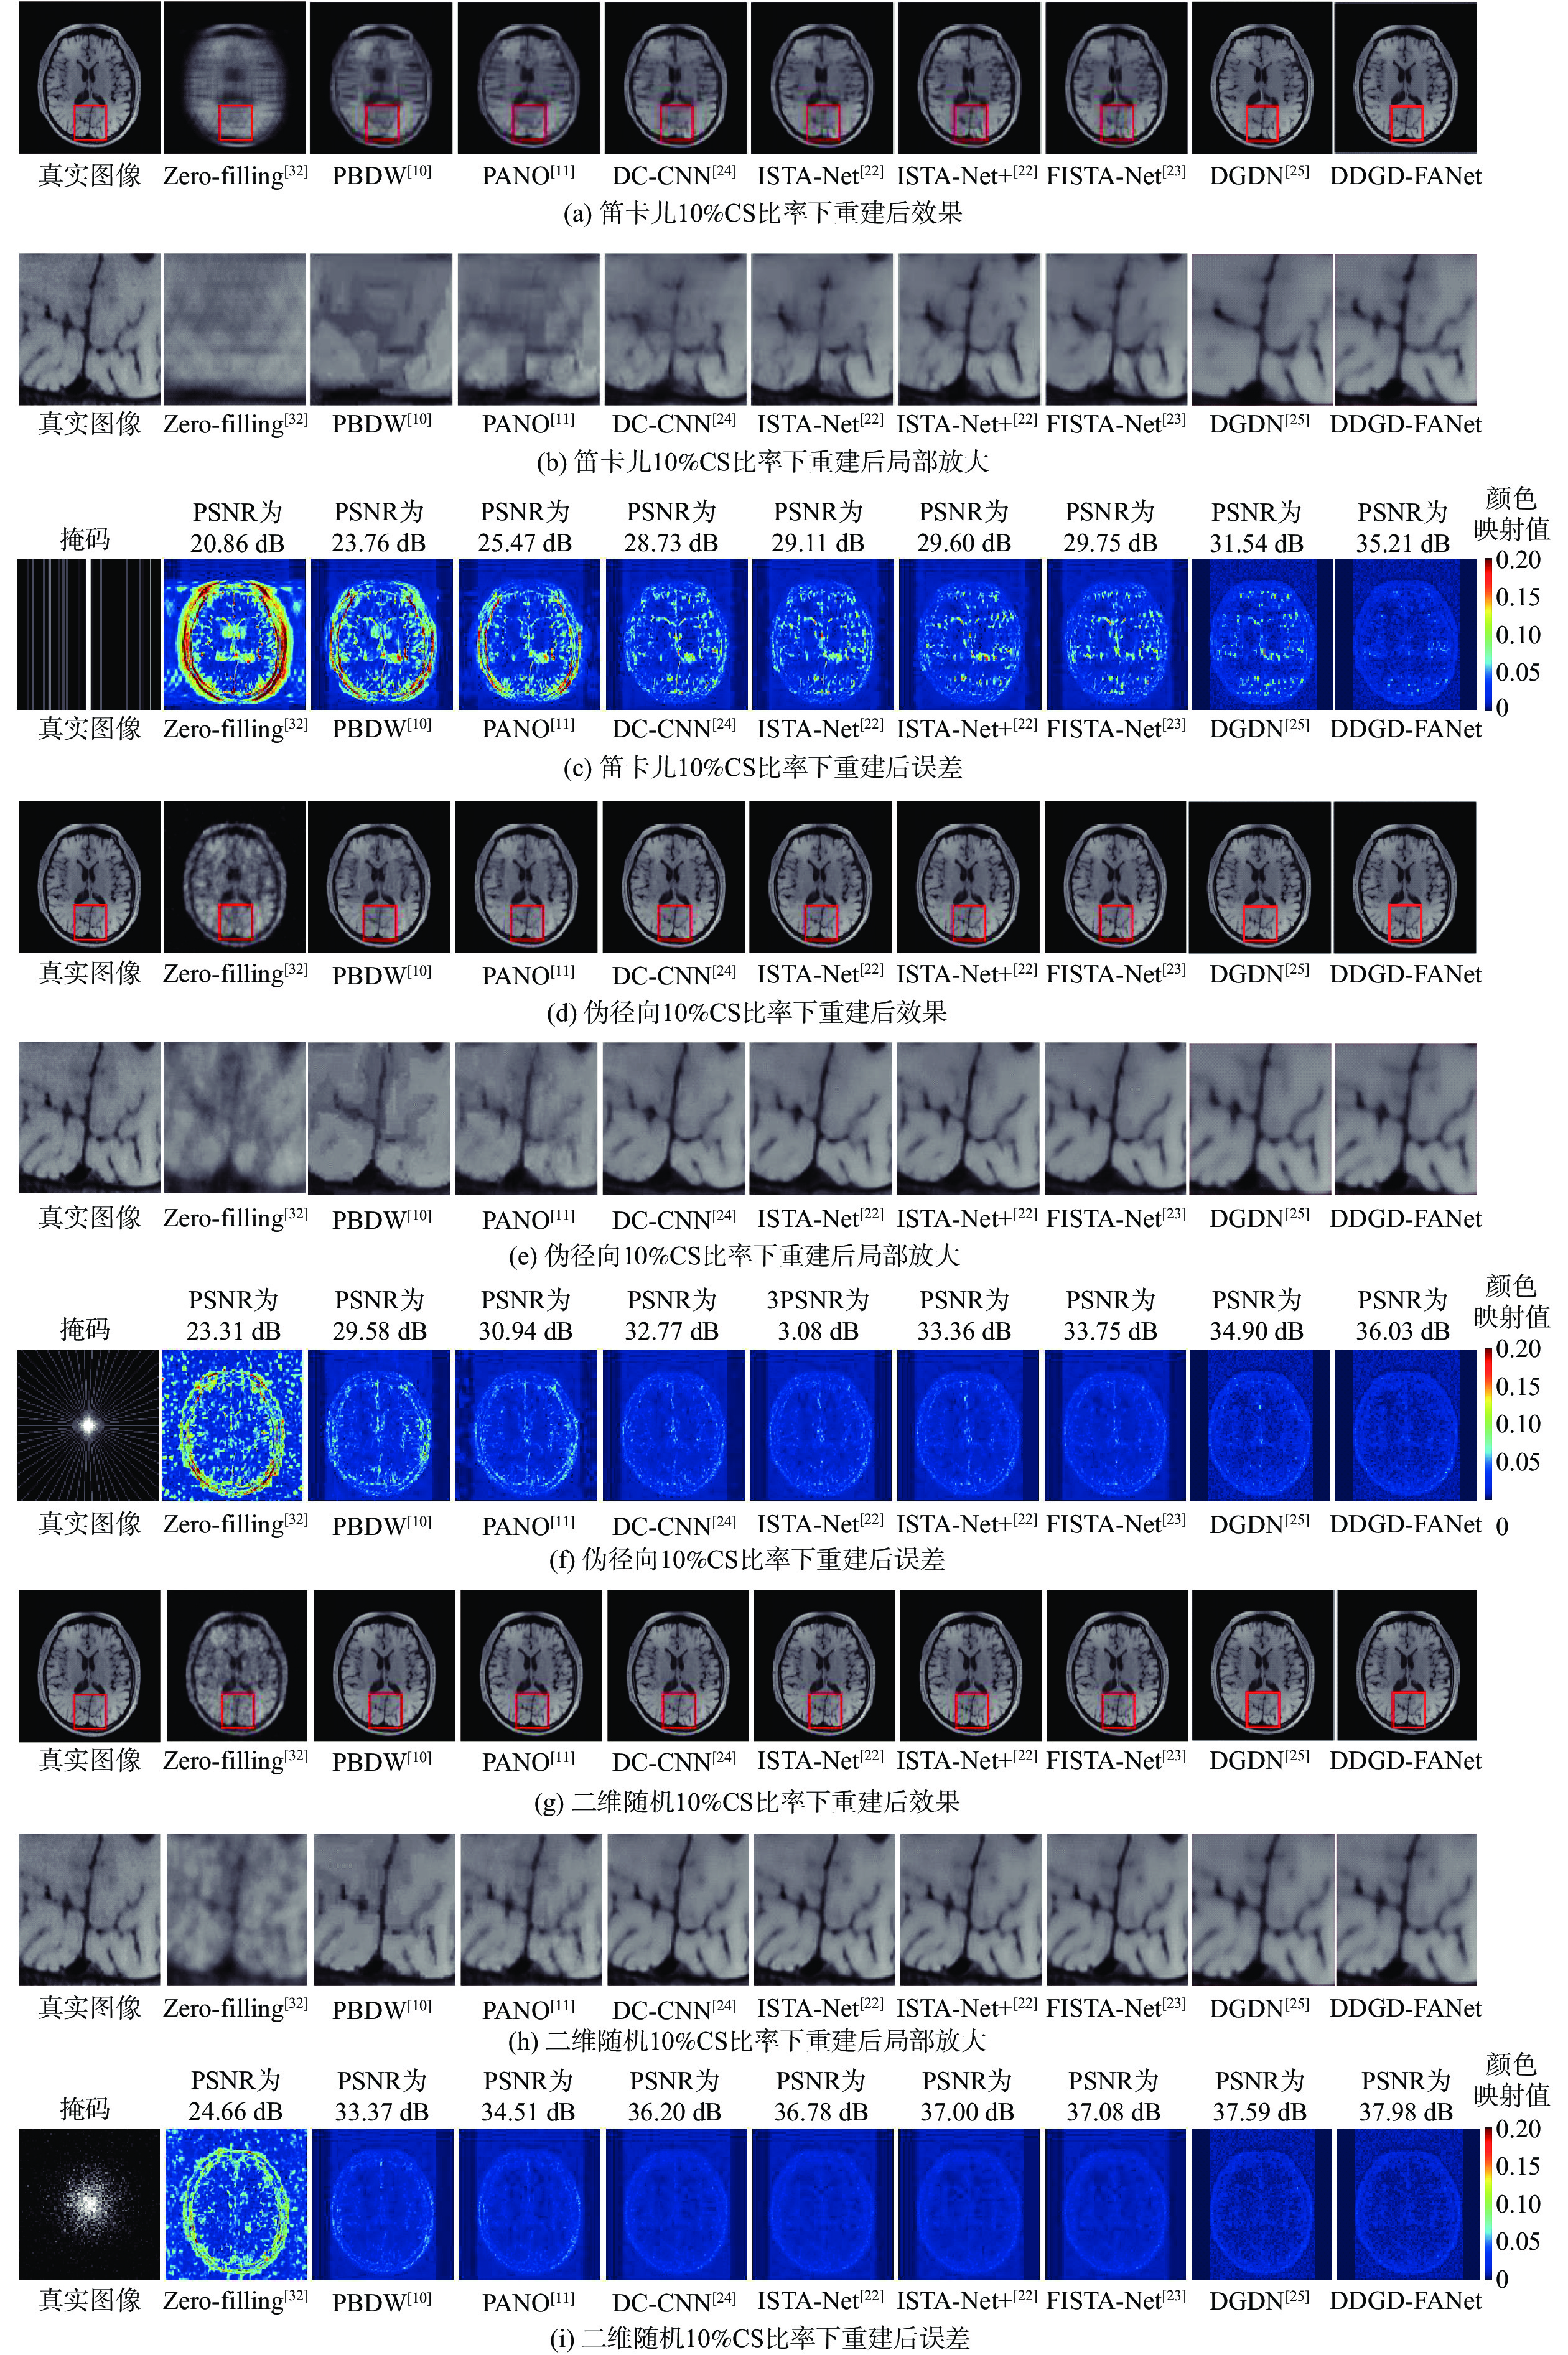

A low-dose CT deep unfolding network based on a sparse transform priors constrain

WANG Yue, ZHANG Xiong, SHANGGUAN Hong, CUI Xueying, ZHANG Pengcheng, GUI Zhiguo

2026, 52(4): 1199-1210. doi: 10.13700/j.bh.1001-5965.2024.0049

Abstract:

Deep iterative unfolding networks have garnered a lot of attention lately because of their great learning capabilities and good interpretability. The regularization terms in existing CT image reconstruction methods mostly focus on information within a specific domain, leading to issues such as edge blurring and information loss in the reconstructed results. Therefore, a sparse transform prior constrain based deep unfolding network is proposed for sparse-view CT reconstruction. Two regularization terms with complementary information—transform-domain sparse regularization and pixel-domain consistency regularization—are created in consideration of the important roles that both pixel-domain and transform-domain information play in picture reconstruction. Based on these, the objective function for sparse-view CT reconstruction is redesigned. Furthermore, a new deep unfolding network for iterative reconstruction of low-dose CT is created by mapping a set of constraint relationships established from an iterative optimization solution for the constructed objective function. Experimental results demonstrate that the algorithm presented in this paper achieves a great improvement on average peak signal to noise ratio (PSNR) and visual information fidelity (VIF) compared to the classical FISTA algorithms.